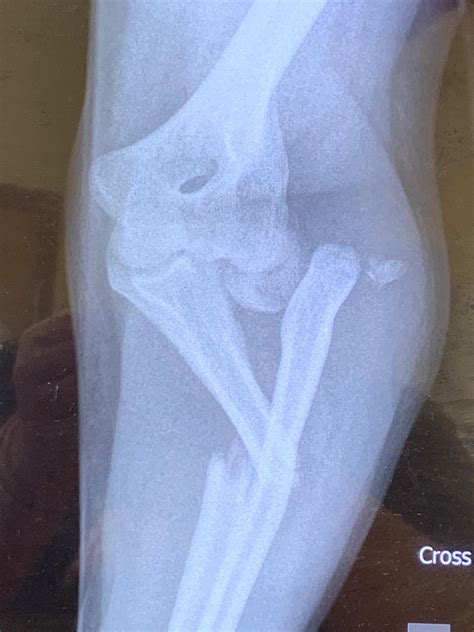

From the Mind of a (Newly Graduated) Chiropractic Student: Radiology #3 ...